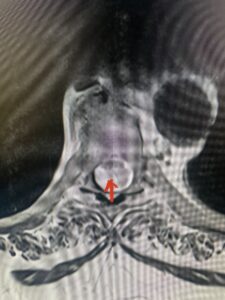

Fig 2a Sagittal and axial T2 weighted cervical MRIs demonstrating large C4 5 herniated disc with spinal cord compression red arrows

This 47-year-old male who four months prior was lifting weights developed sharp pain in his neck. After that he developed progressive numbness in his arms, neck pain and headache. He said that the right arm was worse than the left. On examination the patient had long tract weakness on the right side which included his triceps, finger extensors, hip flexors, and dorsiflexors. The patient did not have hyperreflexia. MRI (Fig. 2) demonstrated a massive, extruded disc herniation with severe cord compression. The patient because of progressive myelopathy and spinal cord compression was indicated for anterior cervical discectomy and fusion at C4-5 (Fig. 3). Patient had significant improvement of weakness and numbness post operatively.

Fig: 2b Axial T2-weighted cervical MRI demonstrating spinal cord compression from C4-5 herniated disc (red arrow)